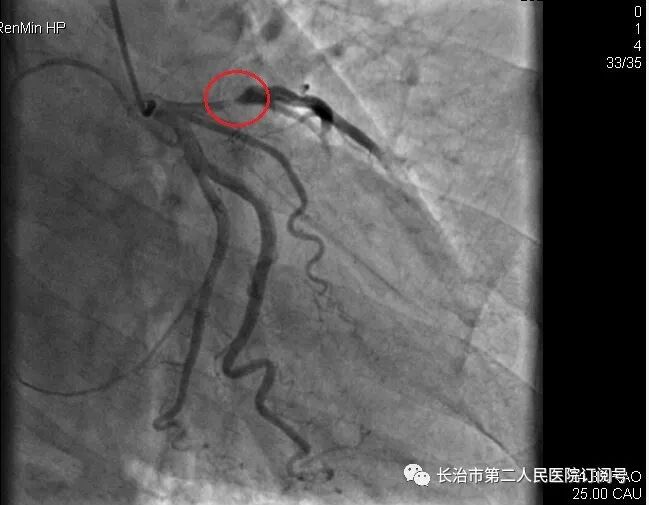

心血管内科李振华医生接诊经详细评估,患者有急诊手术指征,向患者家属交代病情并签手术同意书,急诊科护士积极为患者办理住院手续急诊行冠脉造影提示前降支近段次全闭塞,狭约99%,前向血流TIMI0-1级,术中于前降支植入支架1枚。术后患者胸痛症状完全缓解,各项生命体征平稳,转入CCU继续治疗。

▲植入支架前造影